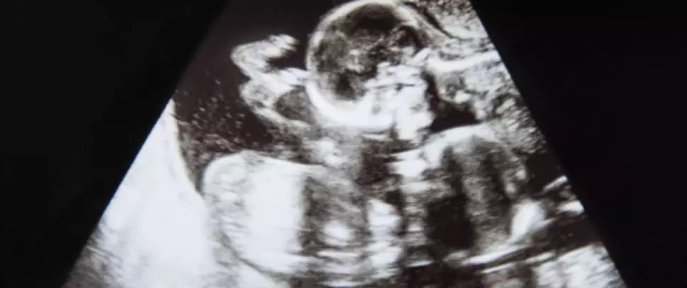

除了同卵双胞胎和异卵双胞胎,你还知道“半同卵”双胞胎吗?在2月28日发表于《新英格兰医学杂志》的文章中,来自澳大利亚布里斯班市的一对双胞胎被确认为世界上第二对“半同卵”双胞胎,也是第一对在妊娠期被临床确认的“半同卵”双胞胎。我们知道,同卵双胞胎是由一个卵子和一个精子结合形成的受精卵分裂而成,因此同卵双胞胎性别相同,并且具有相同的DNA;而异卵双胞胎则是由不同卵子和精子受精发育而成,实际上是两个不同的胎儿,只是同时出 ...